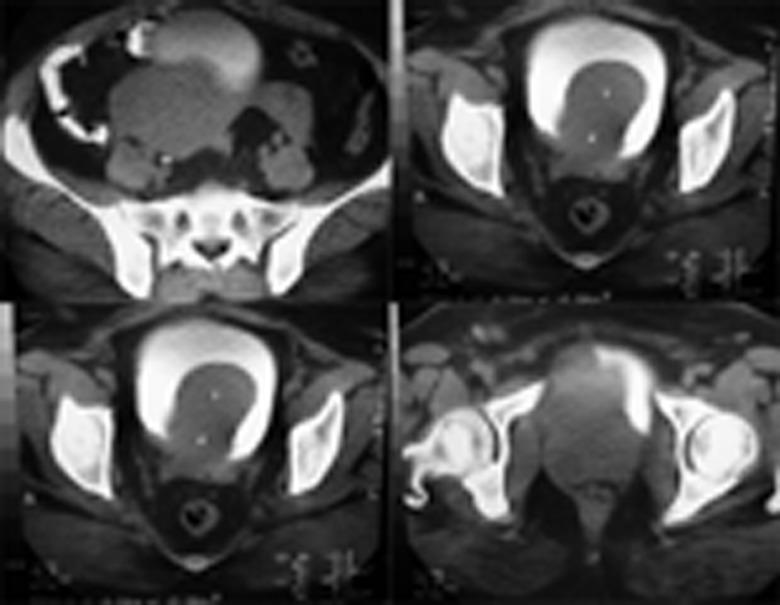

经膀胱剜除膀胱及尿道多发平滑肌瘤

Transvesical enucleation of multiple leiomyoma of bladder and urethra.

Although bladder leiomyoma is rare, this is the most frequent nonepithelial benign tumor of the bladder. Symptoms and treatment depend on location and size of the lesion as well. The optional treatment is a total enucleation or partial cystectomy, although in biopsy proved cases watchful waiting is an option, surgery should be considered as the tumor grows or symptoms are observed. The etiology of bladder leiomyoma is unknown. Uterine leiomyoma is known to be estrogen responsive. The premenopausal women are prevalent in the fourth decade.

尽管膀胱平滑肌瘤很罕见,但它是膀胱最常见的非上皮性良性肿瘤。症状和治疗也取决于病变的位置和大小。可选择的治疗方法是完整摘除或部分膀胱切除术,不过在活检确诊的病例中,密切观察也是一种选择,当肿瘤生长或出现症状时应考虑手术。膀胱平滑肌瘤的病因尚不清楚。已知子宫平滑肌瘤对雌激素有反应。绝经前女性在四十多岁时较为常见。